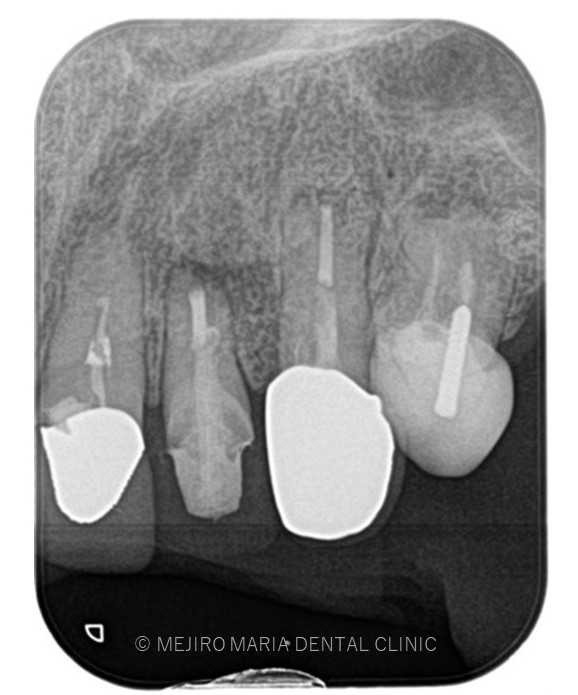

でのリカバリー_該当歯牙の精密根管治療後のレントゲン画像.jpg)

でのリカバリー_歯根端切除術後のレントゲン画像.jpg)

今回の症例は、他院にて歯根端切除術を行った根尖部(歯の根の先)に充填された人工骨の感染が原因と考えられます。

しかし、歯根端切除術の成功率は100%ではなく、多くの症例の中には少なからず再度オペを行うケースも出てくる可能性があります。

歯根端切除術後は術後の透過像で治癒を確認することが重要であり、感染が除去できていれば骨は患者自身の力で自然に再生を行うことになるので、人工骨を充填することはリスクが高い行為であると考えます。